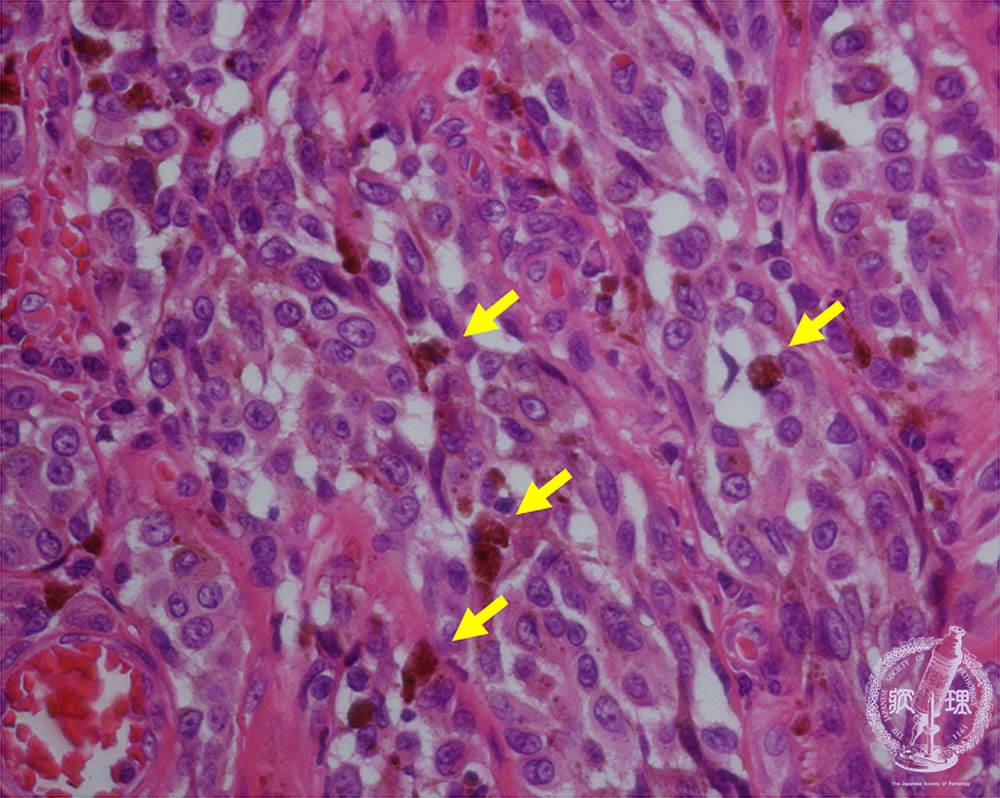

- ★(10)Malignant melanoma

Atypical melanocytes proliferate with anisokaryosis and large nucleoli. Melanin-production is usually but not necessarily seen (arrow).